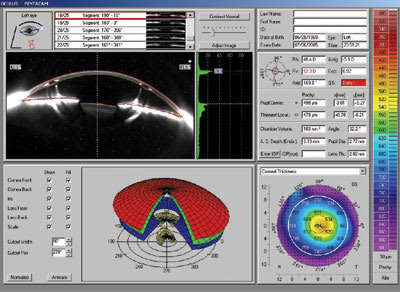

Figure 1. Difference display map of the patient's left eye pre and post corneal reshaping. |

Figure

1 shows the difference display map OS with a –1.87D change in apical power.

The map outlines the margins of the pupil and clearly illustrates a slight temporal

displacement of the 5mm treatment zone.